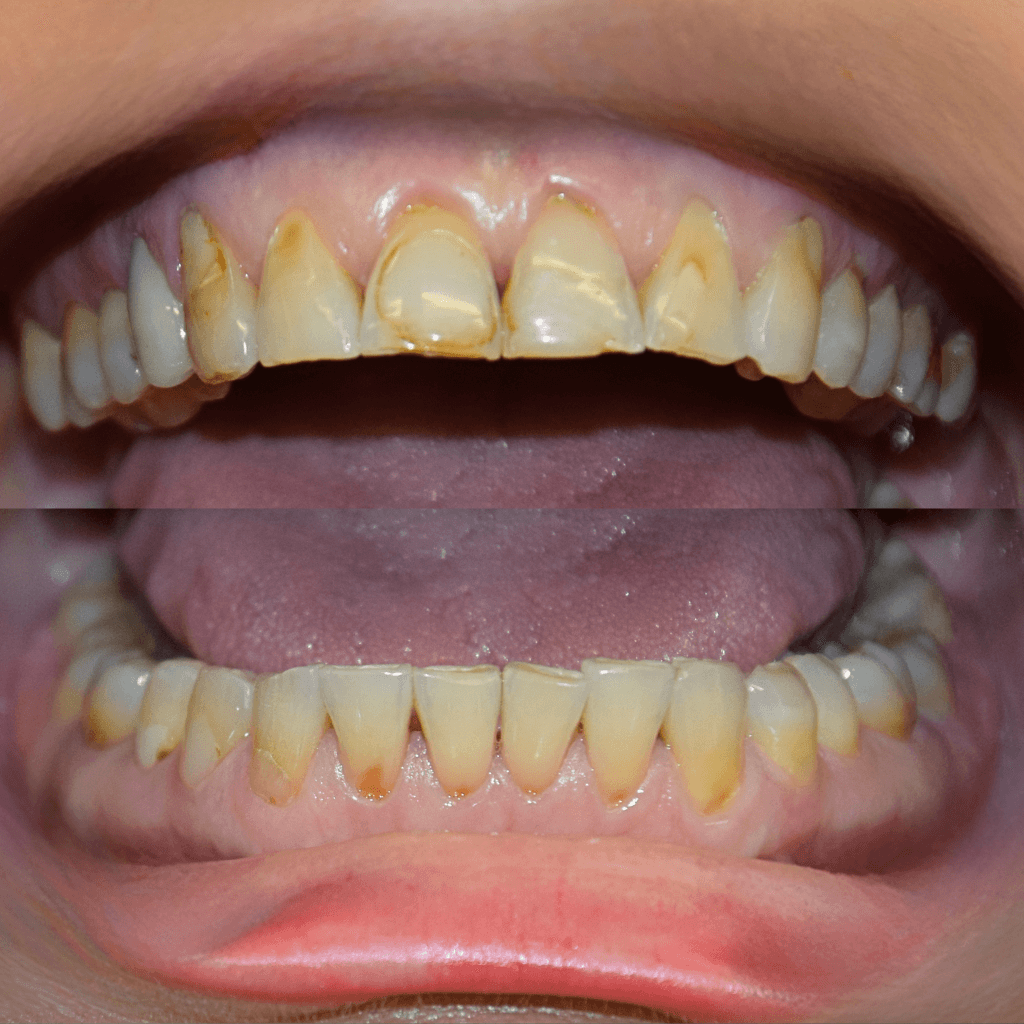

Несъвършенства като цвят, форма, подредба и пропорции на зъбите често влияят повече на увереността, отколкото предполагаме. В много случаи не е необходима радикална намеса, за да се постигне видима и хармонична промяна.

Чрез композитно възстановяване или керамични фасети в Aesthetico постигаме прецизни естетични корекции, съобразени с индивидуалните особености на пациента и с максимално съхраняване на естествената структура на зъба. Резултатът е по-равномерна и балансирана усмивка, съобразена с индивидуалните особености на лицето.